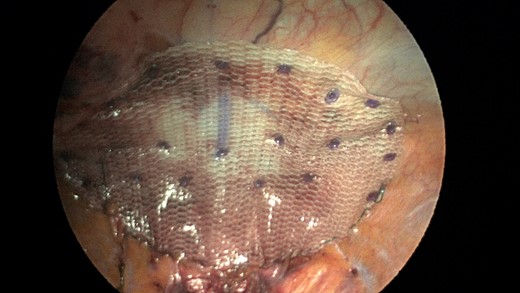

Additionally, another Pariatex composite mesh was then trimmed to 12 cm in width by 9 cm, soaked in vancomycin with local anesthetic and then placed into the abdominal cavity. It was positioned over the area of the repair and fixed into place with absorbable tacks around its caudad edge and centrally. Along the cephalad edge it was fixed with a running V-lock absorbable suture to the diaphragm. Fibrin glue was placed along this same edge (Fig. 7). The ports were removed and incisions were closed.

Completed view of the second main mesh piece placed with overlap of the defect and tack fixation in place.

CT scan is obtained for a specific diagnoses of Morgagni hernia in order to strategize your surgical approach. Minimally invasive laparoscopic techniques have become a popular option in the 21st century due to reduced intraoperative morbidity and quicker recovery rates [9]. Our case was unique in that the novel use of a sleeve of composite mesh was used as a bolster for the Ethibond suture as opposed to felt pledgets so the suture would not pull through the diaphragm. This sleeve of mesh was separate from the main mesh that was used to cover the overall repair (see pictures).